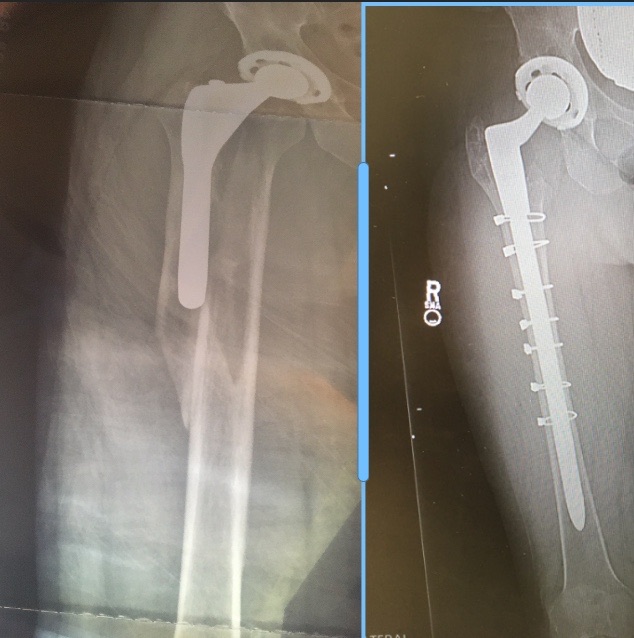

I was ice-skating with my grandson in Hartford, CT when I fell and suffered a “periprosthetic fracture and displaced subtrochanteric fracture of right femur”. I was taken off the ice, transported to a local hospital and transferred to HSS. Dr. Figgie put together a remarkable team, including Dr. Wellman, and they were able to rebuild my femur and implant a new hip stem. Within 12 weeks of my surgery, I back was hiking the Grand Canyon.